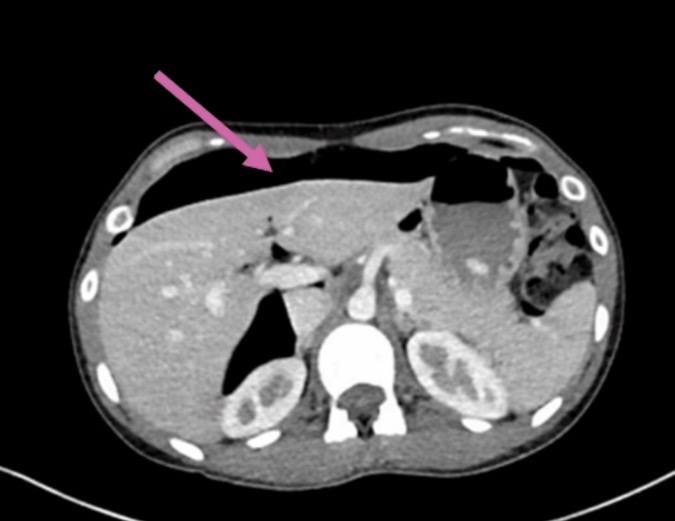

Figure 1. Компьютерная томография, демонстрирующая пневмоперитонеум; воздух отмечен розовой стрелкой.